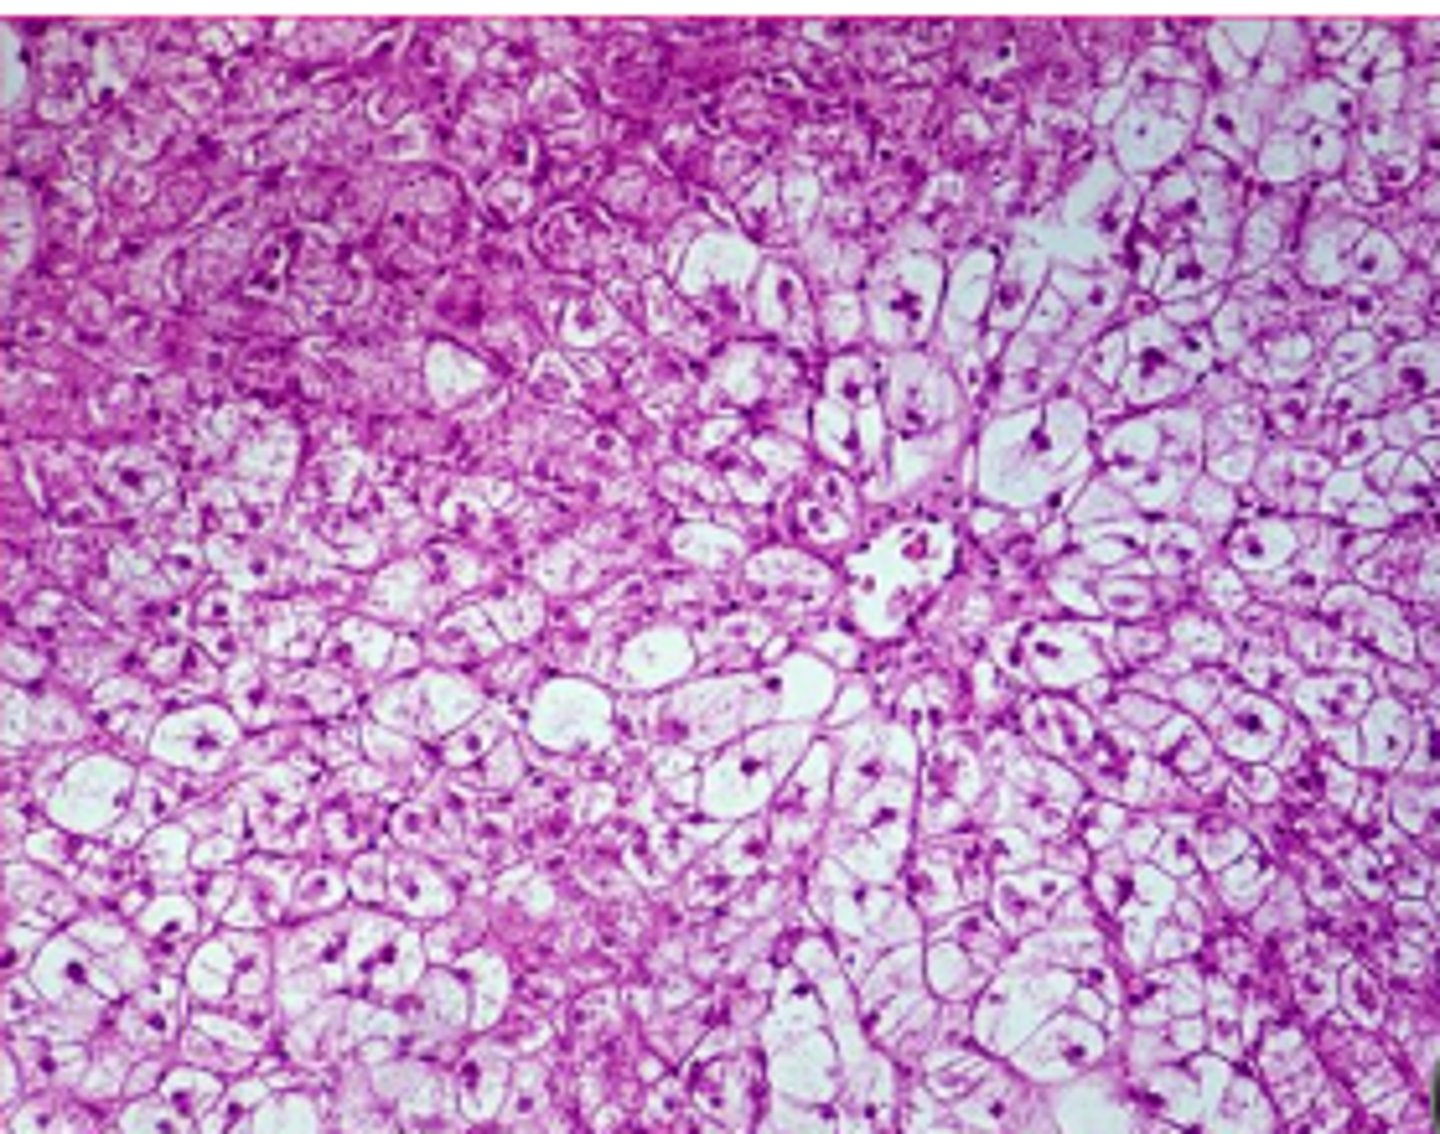

glycogen or lipid?

glycogen

spiderwork webbing of cytoplas, and central nucleus

<p>glycogen</p><p>spiderwork webbing of cytoplas, and central nucleus</p>

lipid

displaced nuclei,

<p>lipid</p><p>displaced nuclei,</p>